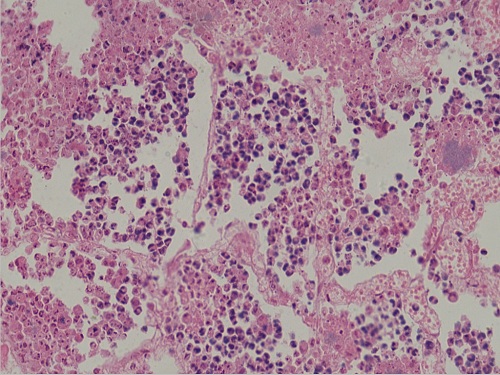

化脓性肺炎3(10X40)

化脓性肺炎4(10X40)